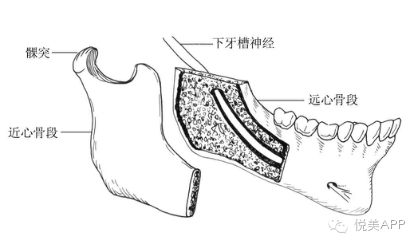

第一种:下颌骨矫正——将下颌骨截骨,去除一段,整体后退,固定,不但缩短下颌的长度,而且在后退的同时伴有上颌骨向上旋转,下颌角的角度变小,侧面也更好看,如果下巴颏太长,还可以缩短。

悦大咖放一个下颌支矢状骨劈开术,大家不要害怕(看懂示意图就可以了)~

切开与显露

矢状与垂直骨切开

劈开下颌支

从矢状面劈开下颌支

移动远心骨段之后~固定

固定

检查咬合并固定